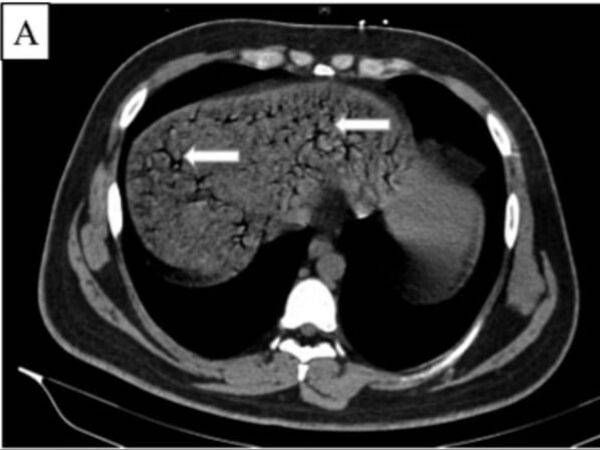

의료진은 컴퓨터 단층 촬영(CT)을 통해 A 씨의 장과 간문맥(장과 간 사이 혈관)에 가스가 비정상적으로 가득 차 있는 것을 확인했습니다.

그러나 A 씨의 간은 이미 심각한 손상을 입은 뒤였으며, 갈수록 상태는 악화했습니다. 결국 A 씨는 병원에서 치료를 받은 지 18시간 만에 숨졌습니다.